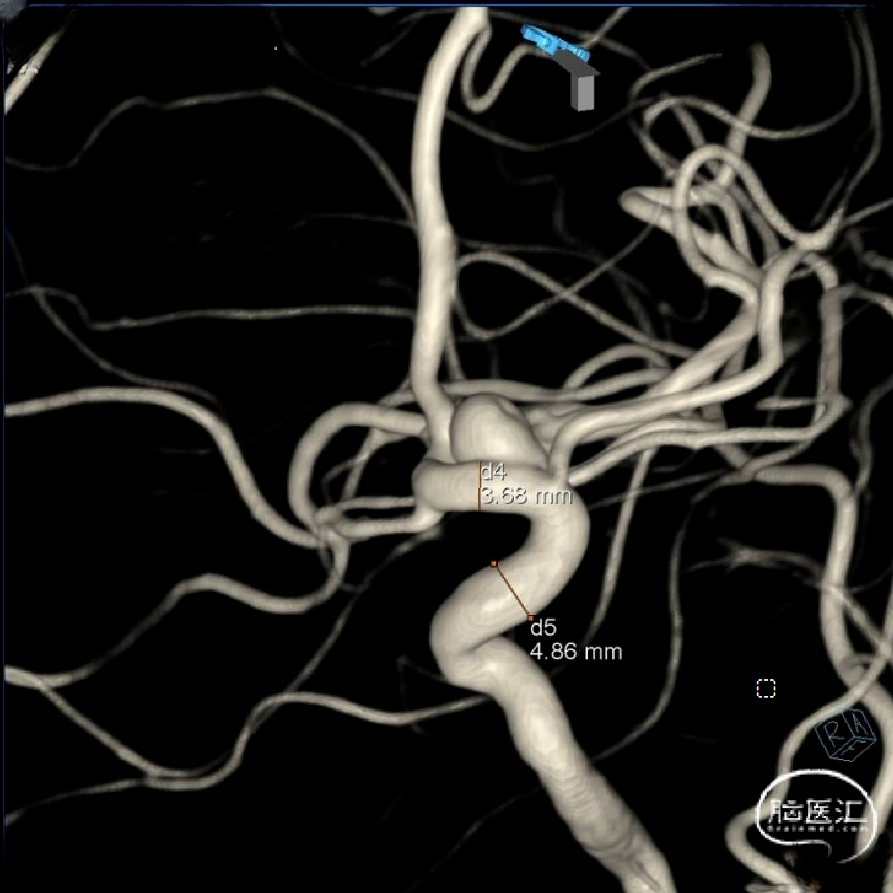

3D造影及测量:

2、术中血管的准确测量、选择合适FD、支架长,避免多弯时打不开或贴壁不好等。

支架系统:血流导向装置Lattice 3.2mm*30mm